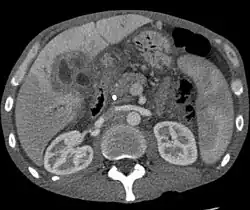

Rakovina jater

U rakoviny jater, tak jako u jiných nádorových onemocnění, dochází k velice rychlému dělení pozměněných buněk. Důsledkem tohoto procesu je většinou vznik nádoru, který negativně ovlivňuje funkci jater. K rakovině může dojít i v důsledku rozšíření nádorových metastáz z jiných, rakovinou postižených orgánů, např. plic nebo konečníku.[1]